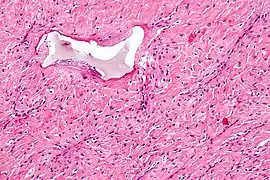

Photo of irritation fibroma on the labial mucosa. High magnification micrograph of a nasopharyngeal angiofibroma.

High magnification micrograph of a nasopharyngeal angiofibroma. Adenoma sebaceum. Multiple wart-like, waxy lumps consisting of angiomatous and fibrous tissue associated with tuberous sclerosis.

AGF lesions share common macroscopic (i.e. gross) and microscopic appearances. Grossly, AGF lesions consist of multiple papules, one or more skin-colored to erythematous, dome-shaped nodules, or usually just a single tumor. Microscopically, they consist of spindle-shaped and stellate-shaped cells centered around dilated and thin-walled blood vessels in a background of coarse bundles of collagen (i.e. the main fibrous component of connective tissue).[2] Angiofibromas have been divided into different types but commonly a specific type was given multiple and very different names in different studies.[2]